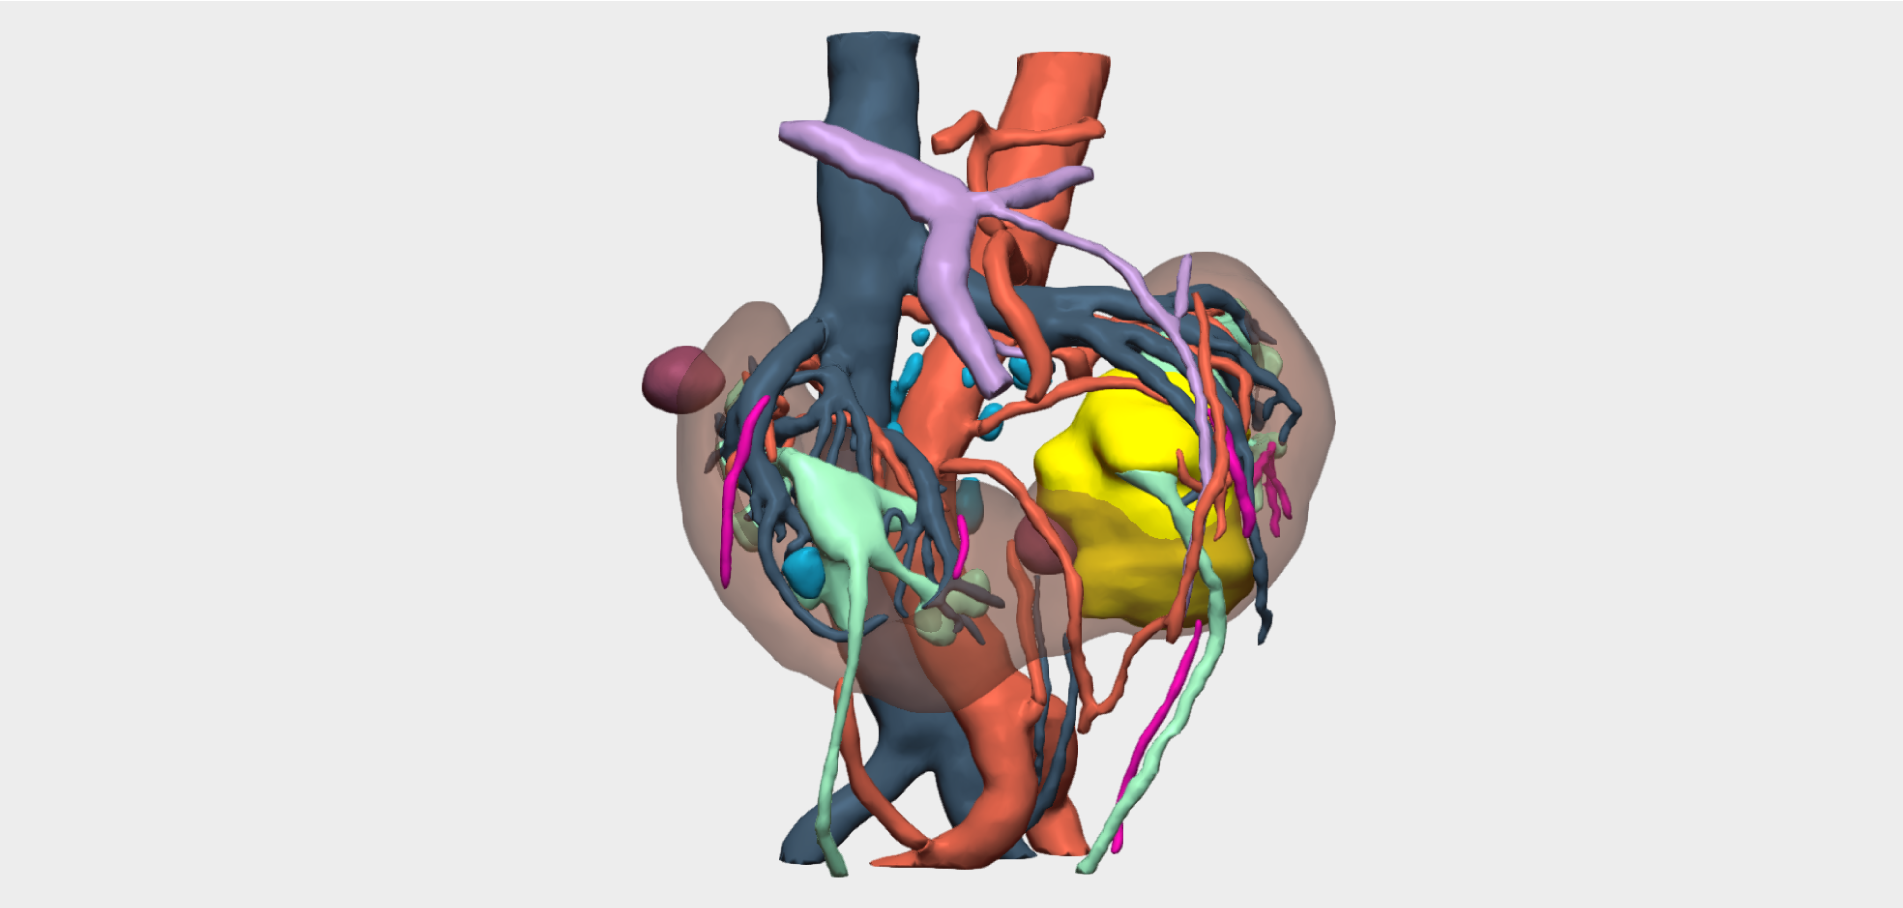

Three-dimensional reconstruction enabled precise localisation of the vascular bifurcation, revealing the presence of two arteries and two veins supplying each renal moiety —an anatomically relevant finding that had not been previously identified and was critical for surgical planning.

Detailed 3D anatomical analysis, combined with advanced functionalities such as arterial territory assessment and the ability to work intraoperatively with dual visualisation —3D reconstruction and laparoscopy displayed simultaneously— was a key factor in the success of the procedure.

To sum it up, in this case, 3D reconstruction enabled detailed visualisation of the renal vascular anatomy, facilitating preoperative planning and optimising the surgical strategy. This approach reduced intraoperative morbidity, shortened operative time and, most importantly, preserved the healthy renal moiety.